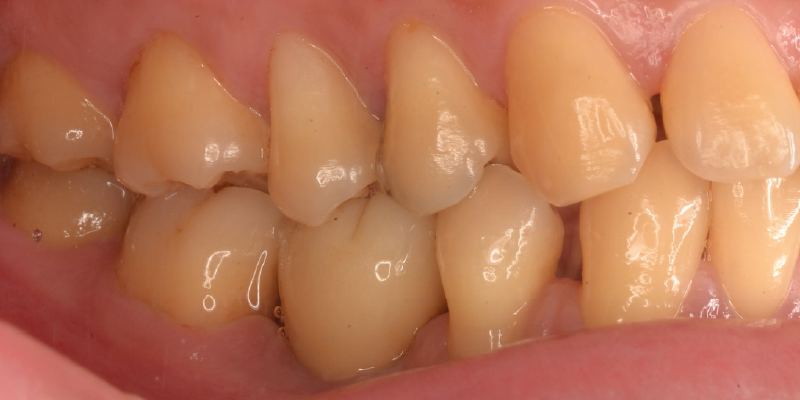

見た目が自然で美しい

インプラントは、人工歯でありながらも、周囲の歯の色や形に合わせて精密に設計されるため、見た目が非常に自然です。口を開けたときに他人から気づかれることはほとんどなく、自信をもって笑ったり会話したりできます。審美性と機能性を両立できるのが、インプラントの大きな特長です。